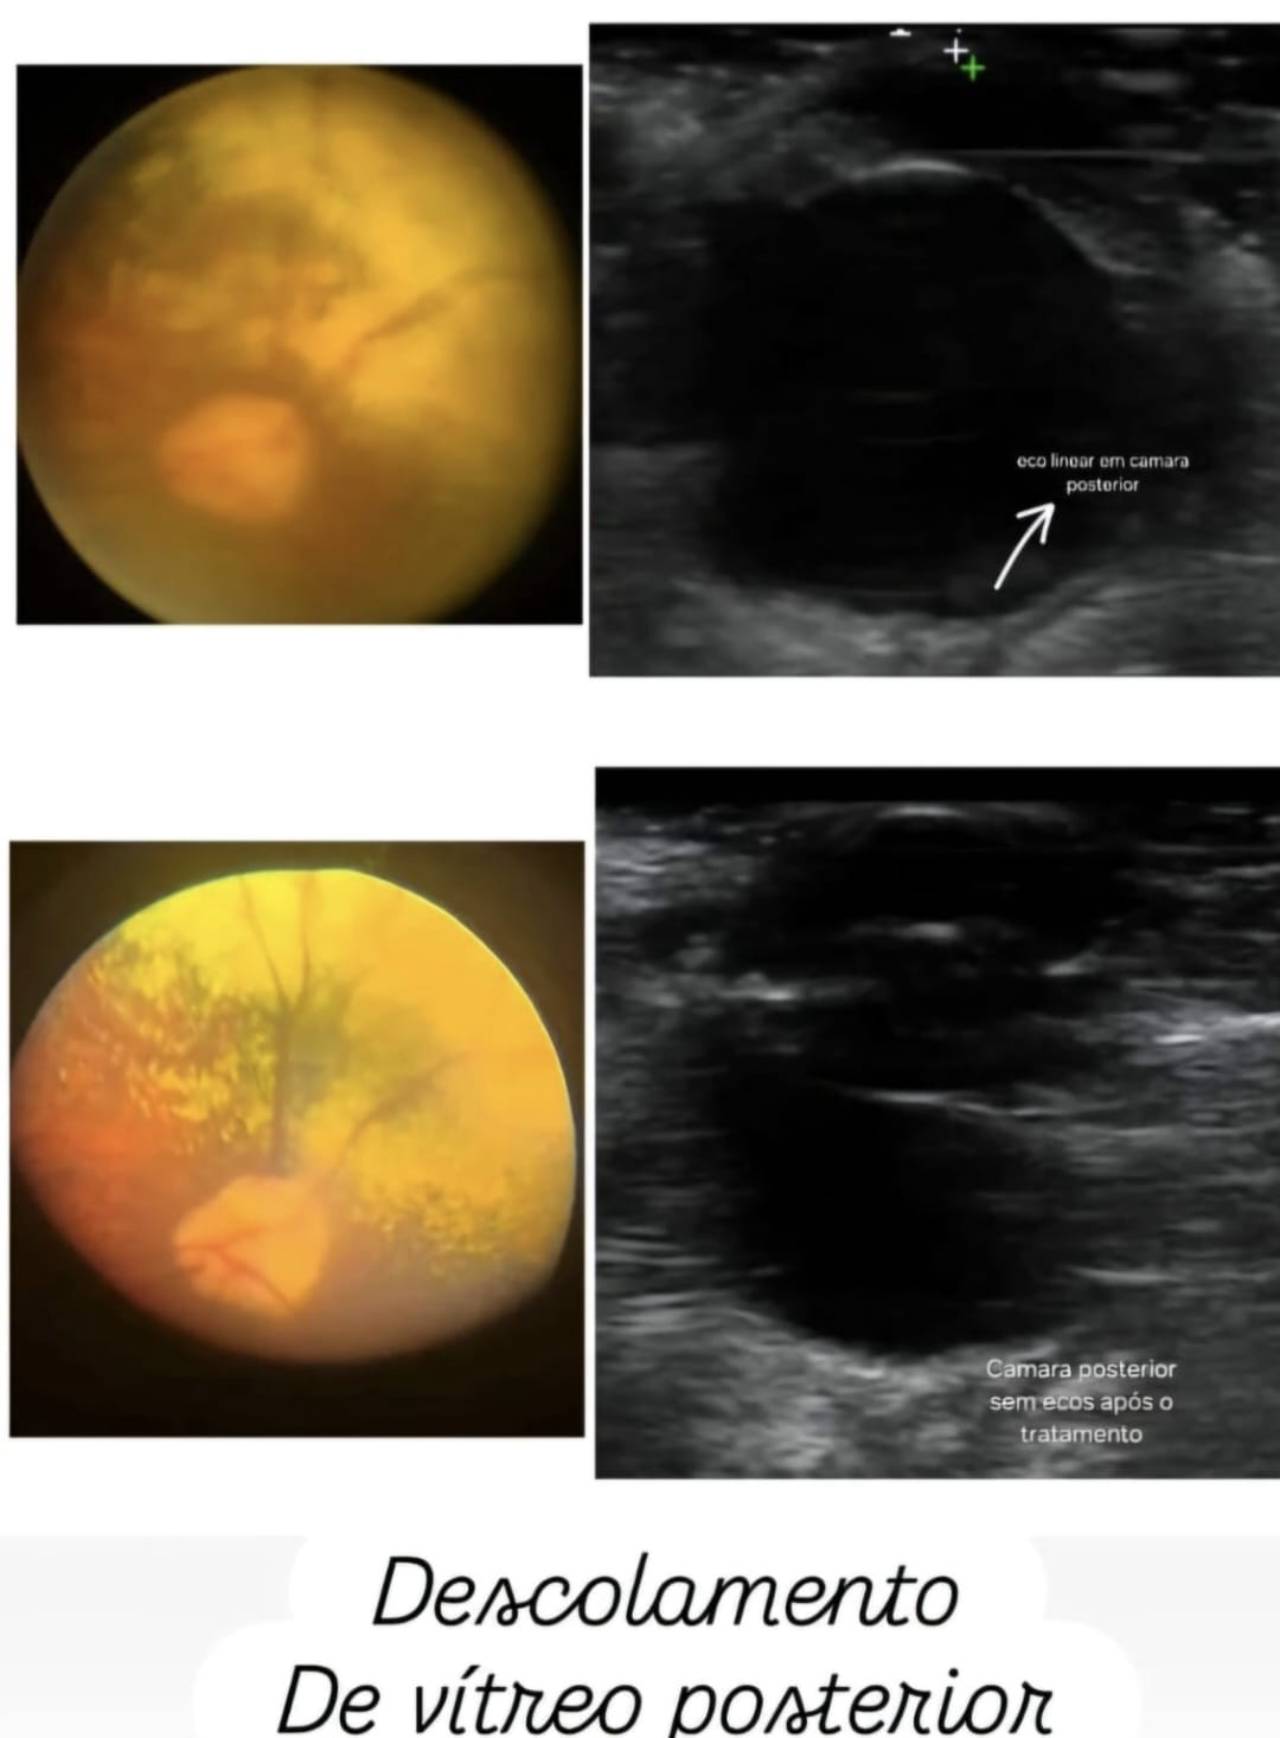

Clínicas VeterináriasO ultrassom ocular é um exame avançado utilizado para investigar alterações no globo ocular e diagnosticar problemas de visão com precisão. Na Clinicão Veterinária, em Três Lagoas – MS, esse recurso é aplicado para avaliar a câmara posterior dos olhos, detectar descolamentos de retina e identificar nódulos retrobulbares, garantindo maior segurança nos diagnósticos.

Esse exame é indicado para animais que apresentam sinais de perda de visão, alterações oculares súbitas, suspeita de tumores ou complicações em estruturas internas do olho. Com mais de 27 anos de experiência em oftalmologia veterinária, a Dra. Claudia Boraschi alia tecnologia de ponta e conhecimento especializado para oferecer diagnósticos confiáveis e atendimento diferenciado.